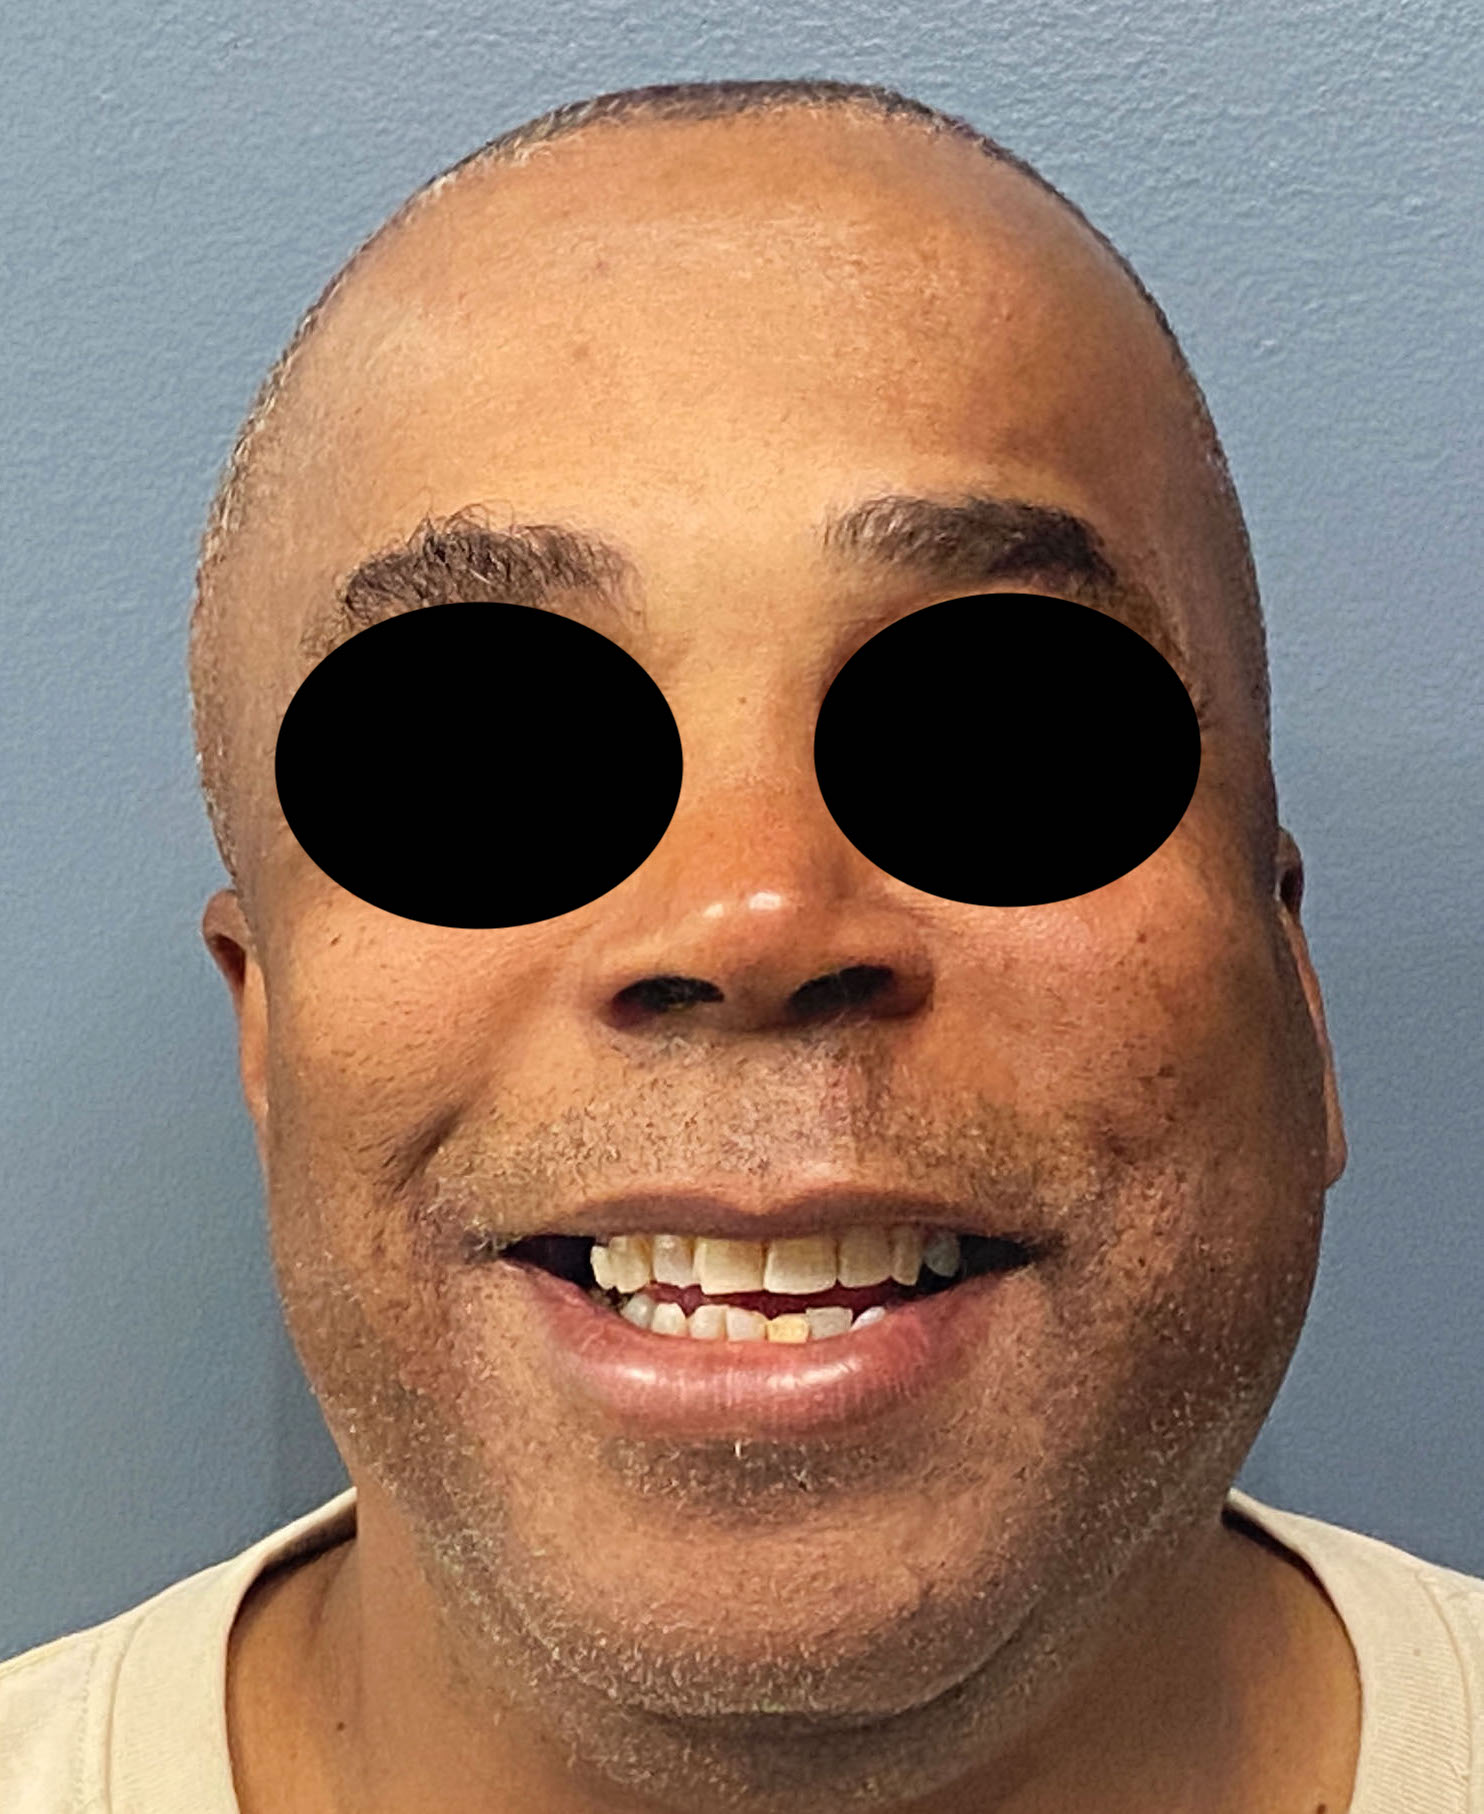

Patient 84

Desire for change of head shape from front view form an inverted V shape to a rounder and wider head shape.

Placement of custom extended forehead-temporal implants through incisions in the crease behind the ear. (he had a prior back of head skull implant which is green in the implant designs and which the head widening implants partially covered it)

Desire for change of head shape from front view form an inverted V shape to a rounder and wider head shape.

Placement of custom extended forehead-temporal implants through incisions in the crease behind the ear. (he had a prior back of head skull implant which is green in the implant designs and which the head widening implants partially covered it)